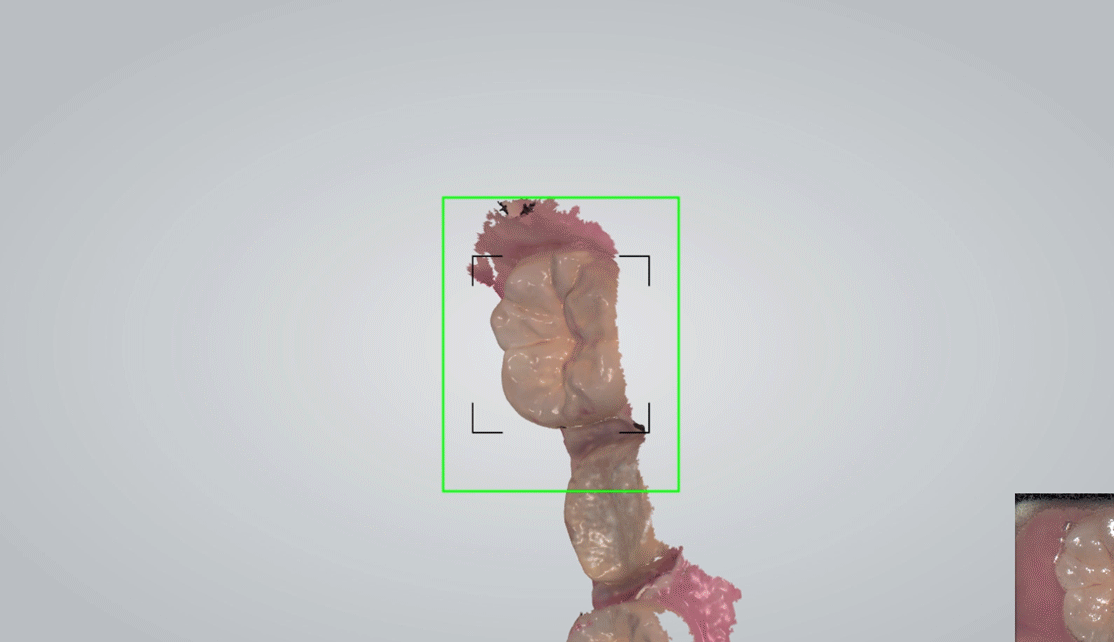

• STEP 02

수술부위 스캔하기

CT와 구강스캔 데이터를 결합해 수술 전 3D 시뮬레이션으로 식립 위치·각도·깊이를 정밀 계획합니다.

CT와 구강스캔 데이터를 결합해, 신경·혈관·골의 두께까지 고려한 3D 시뮬레이션을 통해 최적의 식립 위치를 결정합니다.